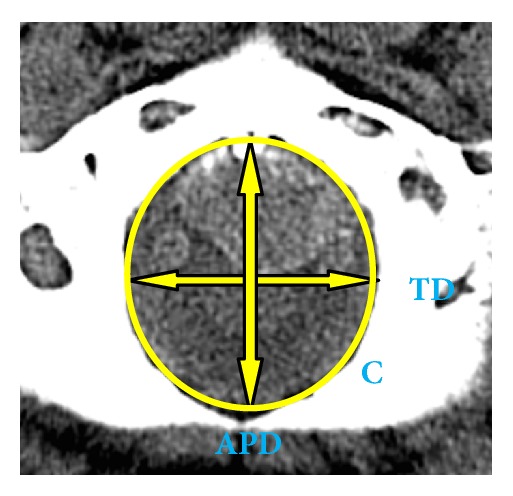

Materials and methods: The study sample comprised 200 CT scans (110 males and 90 females) of south Indian origin. The shapes of the foramen magnum were classified into 8 types: oval, egg, round, tetragonal, pentagonal, hexagonal, irregular (A), and irregular (B). The parameters were noted meticulously and the statistical analysis for sex comparison was made by Student's t-test and was considered significant whenever P≤0.05. To determine the relationships between the studied parameters, Pearson correlation coefficients were calculated.

Results: The foramen magnum was classified into 8 types based on shape. Commonest was oval and pentagonal was the least common type. The anteroposterior diameter, transverse diameter, circumference, and area were significantly greater in males than in females (P<0.001). The mean FM index of male CT scans was 85.01 ± 8.67, whereas in case of female CT scans, it was 83.17 ± 7.78. With all the variables in consideration, overall 65% of cranial CT scans were sexed correctly by using multivariate analysis.